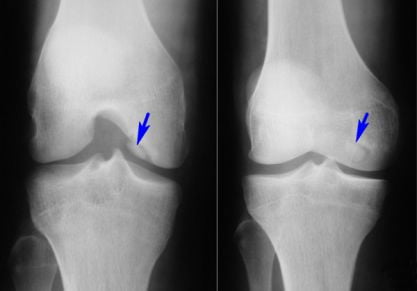

Остеоартрит коленного сустава: симптоматика и тактика терапии

Как лечится остеоартрит коленного сустава медикаментозно и хирургически? Помогает ли народная медицина? Как не навредить себе?